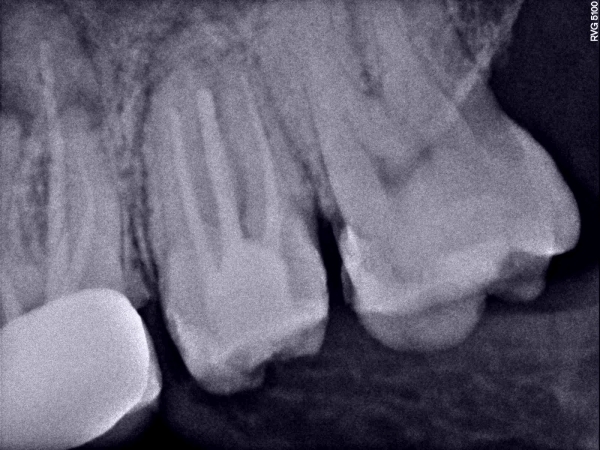

Хочу поставить коронки на передние 4-е зуба, из них 2-живых и 2 с пломбированными каналами (20 лет назад). На снимках воспалений у пломбированных каналов нет, каналы сделаны хорошо. Можно без последствий установить коронки на такие зубки, или нужно перелечивать/лечить каналы?

• Необходим осмотр и анализ прицельных рентгеновских снимков. Если на них действительно нет воспалительных процессов, корневые каналы механически обработаны качественно, пломбировочный материал плотной консистенции и прослеживается на всем протяжении корневого канала и до верхушки корня зуба, тогда такой зуб можно не перелечивать , а сразу после ортопедической подготовки восста читать далее